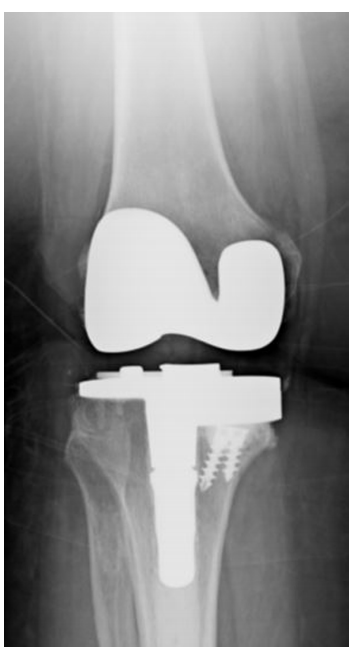

固定轴承(FB)(图3)和移动轴承(MB)(图4)是UKA的两个主要设计概念。尽管MB假体相对于FB设计的理论优势使其越来越受欢迎,聚乙烯制造的改进显著降低了FB设计中的磨损,由于聚乙烯磨损不再是FB设计的主要问题,因此UKA的设计选择仍然存在争议。

图3:固定轴承内侧UKA的X光片。

图4:可移动的内侧UKA的X光片

一些元分析比较了FB和MB设计。Peersman及其同事回顾了44项比较和非比较研究,涉及9463个膝关节。按年龄和随访时间分层后,FB植入物和MB植入物的生存率无明显差异。然而,MB膝关节的平均翻修时间较短,分别为2.5 – 1.8年和6.7 – 2.5年(P<0.001)。在另一项比较FB和MB UKA的荟萃分析中,Cheng和同事检查了9项研究,涉及915个膝盖。他们还发现,在临床结果评分、活动范围或翻修率方面,植入物之间没有显著差异。与Peersman及其同事相似,他们发现MB患者翻修时间明显提前(FB植入物5.0 vs 6.3年),MB患者由于轴承脱位导致早期失败。在FB组中,后来的失败更常见的原因是聚乙烯磨损。Smith及其同事确定了5项比较FB和MB植入物用于内侧和外侧UKA的研究,分别涉及165和159个膝关节。在医用UKA的临床结果方面,植入物类型之间没有显著差异,并发症发生率也没有差异。

总之,UKA在FB和MB设计之间的任何决定都受到缺乏可靠和设计良好的研究的缺陷,而且证据基础仅限于观察性研究和小型随机对照试验。然而,这两种植入物之间似乎没有什么大的区别。